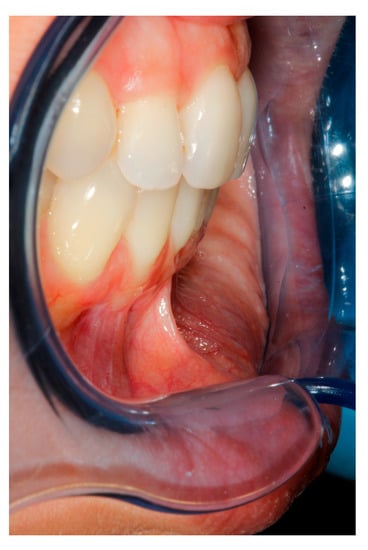

2. Case Study